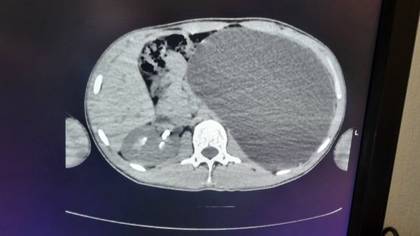

Новосибирские врачи удалили 17-летнему юноше почку размером с пятилитровую бутылку, которая занимала почти весь объем живота. По словам медиков, такое отклонение было «бомбой замедленного действия». Об этом в среду, 18 февраля, сообщили в пресс-службе регионального Министерства здравоохранения.

— У нашего пациента почка достигла размеров пятилитровой бутылки! Она занимала почти весь объем живота и давила на все соседние органы. Это была настоящая «бомба замедленного действия»: любая травма, случайный удар в живот — и мешок мог разорваться внутри, — сказали в ДГКБ № 1.

В ведомстве рассказали, что хирурги откачали всю скопившуюся жидкость через четыре небольших прокола и удалили орган. Врачи уточнили, что пациент уже идет на поправку, сказано на сайте Минздрава.